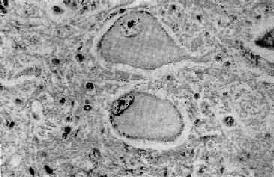

1.中央性Nissl小体溶解(central chromatolysis)这是一种可逆性变化,病因一旦去除,就可恢复正常,如病变继续发展,则可导致细胞的萎缩和死亡。常见的病因有病毒感染(如脊髓灰质炎病毒)、维生素B属缺乏、坏血病和神经元与轴突断离。病变表现为神经细胞肿胀,丧失典型的多极形状而变为圆形,胞核偏位,胞浆中央的Nissl小体崩溃成为细尘状颗粒,进而完全溶解消失,或仅在细胞周边部有少量残余。胞浆着色浅而呈苍白均质状(图16-1)。

中央Nissl小体溶解

图16-1 中央Nissl小体溶解

神经细胞肿胀,胞核偏位,Nissl小体仅见于细胞周边部